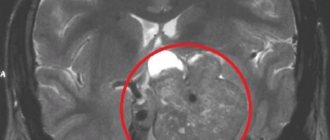

1. Вот, например, (Рисунок 15) в красном кружочке — это гигантская аденома гипофиза

. В данном случае это была пролактинома с супраселлярным ростом кверху и с инфраселлярным ростом книзу. Верхние — это до операции, нижние — это после операции. Но, как видите, опухоль удалена полностью. Пациентка наблюдается уже несколько лет и все хорошо. Операция выполнена в одну сессию, через нос.

Рис. 15 Клинический случай, гигантская аденома гипофиза